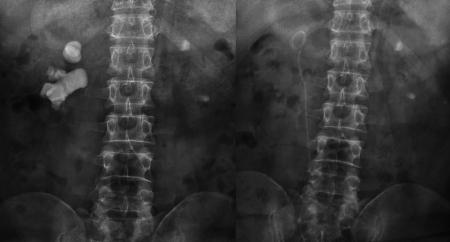

宋先生術(shù)前與第二次術(shù)后的結(jié)石對(duì)比宋先生術(shù)前與第二次術(shù)后的結(jié)石對(duì)比

又進(jìn)行了20多次體外碎石后,腎結(jié)石非但沒(méi)打掉,反而長(zhǎng)到了駭人的8公分:X光片里面形似一顆“老姜”,幾乎塞滿了右腎內(nèi)的大小通道。

“泌尿道梗阻;右腎多發(fā)結(jié)石、中度擴(kuò)張積水;左腎結(jié)石伴左腎積水,左腎縮小。”醫(yī)院的檢查結(jié)果顯示,結(jié)石充滿了宋先生的右腎,右腎功能受結(jié)石和積水的影響,僅剩4成左右,而左腎則出現(xiàn)了可怕的腎萎縮。而這些正是在宋先生接受了驚人的100多次體外沖擊波碎石,累計(jì)花掉20多萬(wàn)元后,付出的沉重代價(jià)。

“人的腎臟約長(zhǎng)10-12厘米,普通人兩、三厘米的結(jié)石,就算比較大的了,而宋先生的腎結(jié)石一年多時(shí)間,就在腎臟內(nèi)迅速長(zhǎng)到8公分。如此驚人的生長(zhǎng)速度,在臨床上十分罕見(jiàn)。”宋先生的主刀專(zhuān)家、四川結(jié)石病醫(yī)院泌尿一科易成然主任介紹。